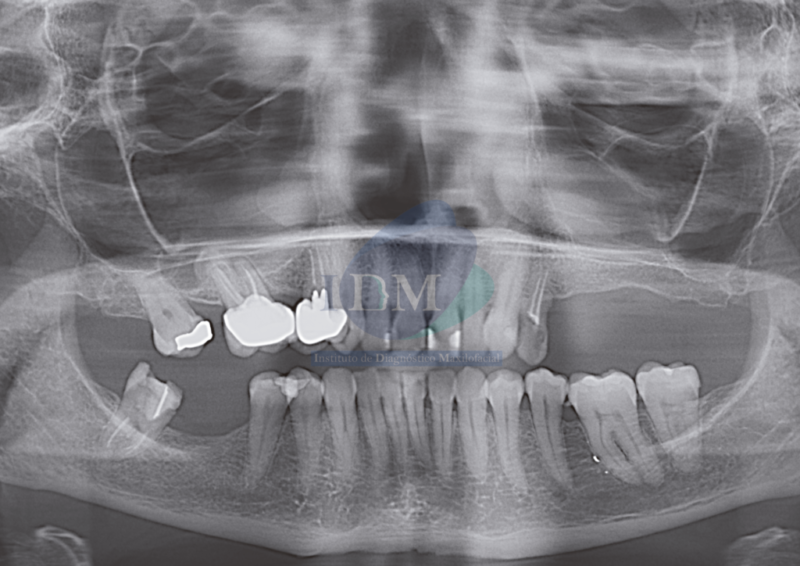

Radiografia Panorámica

A la evaluación de la radiografía panorámica se aprecia mineralización del proceso estilohioideo bilateral, neumatización de ambos senos maxilares, además se visualiza presencia de placa cervical mineralizada, reabsorción ósea del proceso alveolar y múltiples piezas con presencia de obturación de conductos. La pieza 26 presenta procesos osteolíticos periapicales y corona protésica. Asimismo, se observó una imagen radiopaca de forma redondeada y limites definidos que se proyecta sobre el cóndilo mandibular del lado izquierdo, se realizó la ampliación del estudio con una tomografía cone beam.